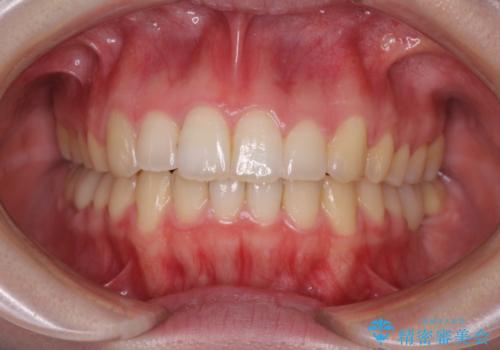

- 小さいころからの歯の変色と矯正治療の後戻りを気にして来院された患者様です。

気になる変色歯を仮歯に変え、その後歯列不正を矯正治療で改善し、最後にオールセラミッククラウンにて補綴治療することとしました。

数十年に及んだ歯の変色が改善されたため、大変満足していただきました。